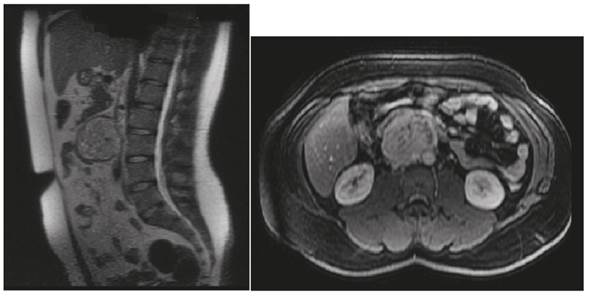

Los resultados de los siguientes exámenes de laboratorio fueron normales: perfil tiroideo, función hepática, paratohormona, calcitonina, perfil inmunológico, ecocardiograma y doppler renal y extraadrenal. El nivel de ácido vanilmandélico en la orina fue de 18,9 mg/24 horas (normal hasta 13,6), metanefrinas 1,9 mg/24 horas (normal hasta 1,0), adrenalina 16,8μg/24 horas (normal hasta 20), noradrenalina 2272,5μg/24 horas (normal hasta 90). La resonancia magnética abdominal simple y contrastada mostró una masa de aproximadamente 63 x 65 x 61 mm, situada anterior a la aorta y a la vena cava inferior (Figura 1).